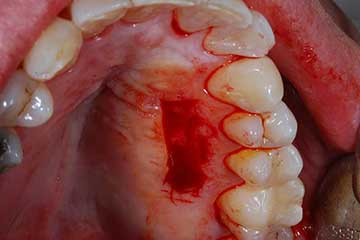

Lembo libero per correggere una recessione gengivale